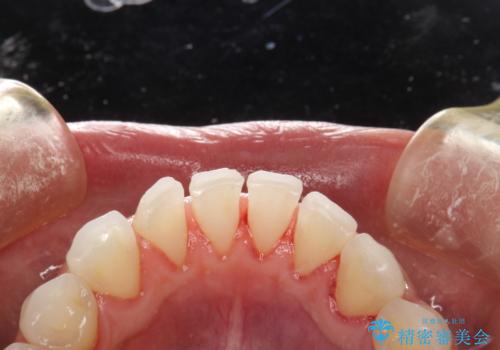

- 痛みや特に気になるところはないが、しっかりとクリーニングしてほしいとのことで来院された患者様です。PMTC 30分コースでのメンテナンスを行いました。

歯を長持ちさせるために、1番の対策が、PMTC を定期的に行うことです。虫歯や歯周病の予防・再発の予防などと、患者様の歯の健康を保つためプロフェッショナルクリーニングを行っています。

痛みや症状が無くても、歯科医院にて専門的なクリーニングを行うことが大切です。